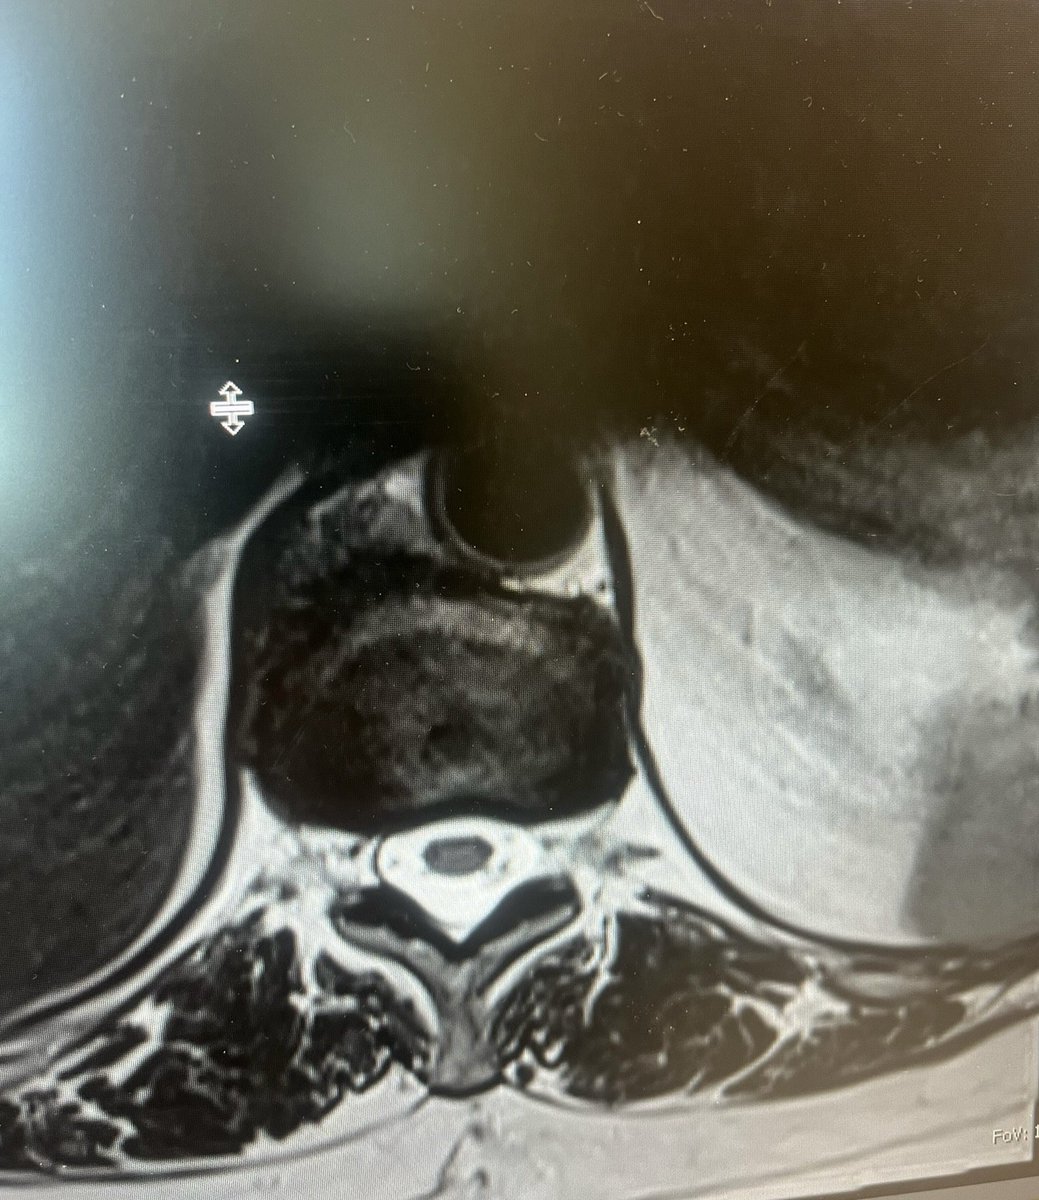

Patient with 3 months of left-sided pain in L3 distribution but w/o motor/sensory deficits. MRI shows an L3/4 disc herniation...that is anterior, with no central canal, lateral recess, or foraminal compromise. I encounter this once a year. Thoughts and insights?